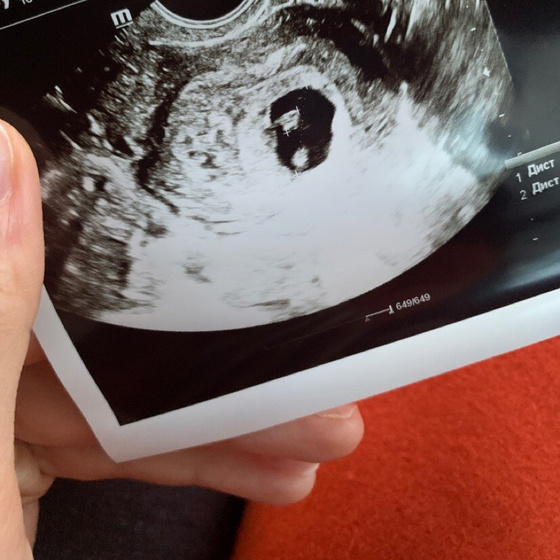

Мы сегодня были на контрольном узи?

Сердцебиение есть, все отлично. Никаких отслоек, гематом и тонуса нет.

Развиваемся как положено сроку❤️

Здорово, сколько у вас свд и ктр?

Ктр 5,6